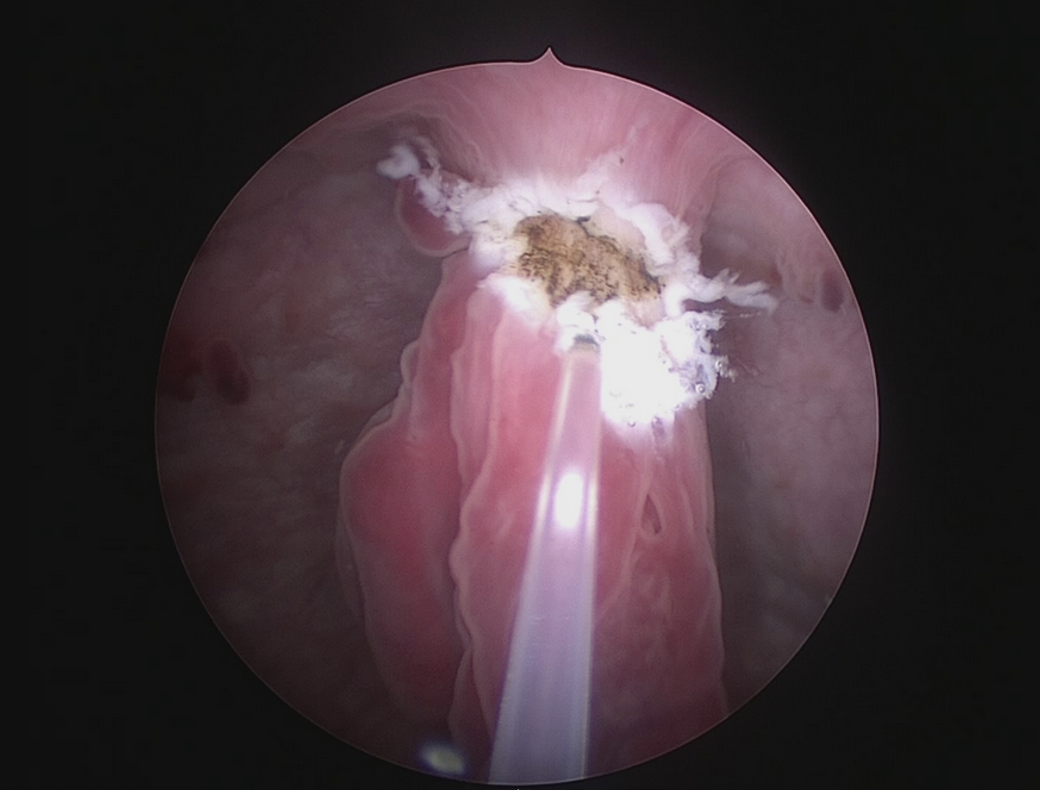

Zystoskopischer Blick auf Harnblasenpolypen

Zystoskopischer Blick auf einen Harnblasenpolypen (Abb. 1) während der endoskopischen Laserresektion mittels 400 µm – Faser (Dauerstrahlmodus, Kontaktverfahren, 5 mm/sec). Der Schleimhautüberzug des Polypen wurde mit 6 Watt 1470 nm durch einen Querschnitt am Polypenstiel eröffnet. Es verblieb ein weißlicher Schnittrand, in dessen Tiefe der gut durchblutete Polypenstiel mit 6 Watt 1470 nm und 3 Watt 980 nm im Verlauf schichtweise koaguliert und durchtrennt wird. Die Koagulation hinterlässt ein bräunliches Wundbett. Eine Karbonisation, also eine Schwärzung, ist nicht erwünscht, da durch verkohltes Gewebe eine Isolierschicht gegenüber Laserstrahlen aufgebaut wird.